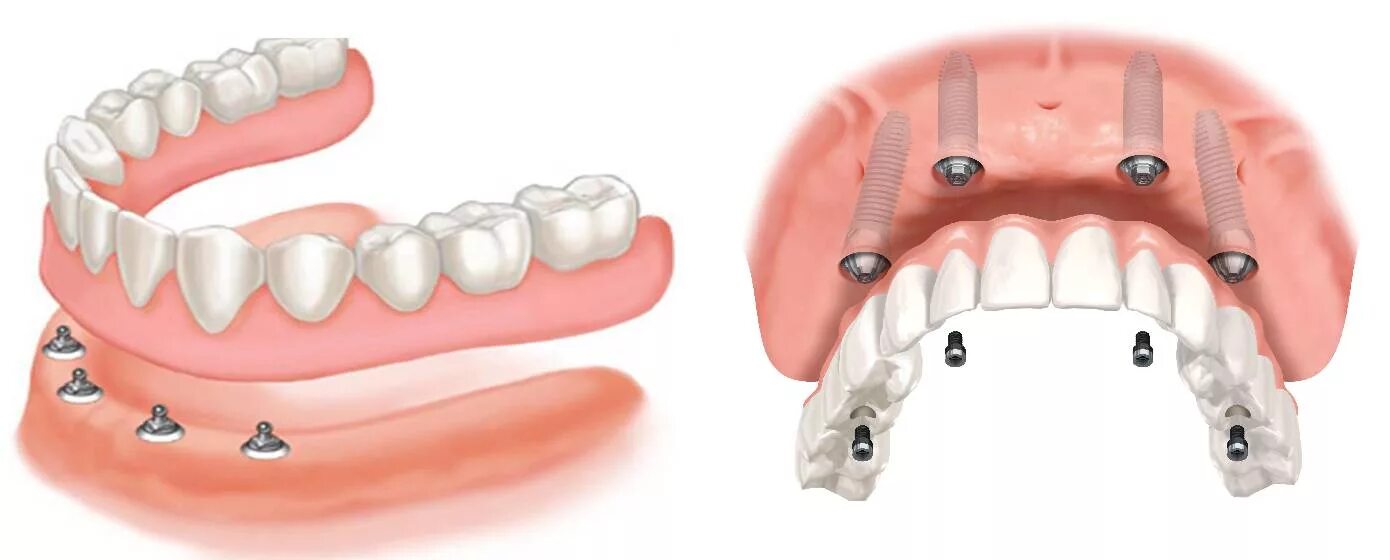

Поставить 4 зуба